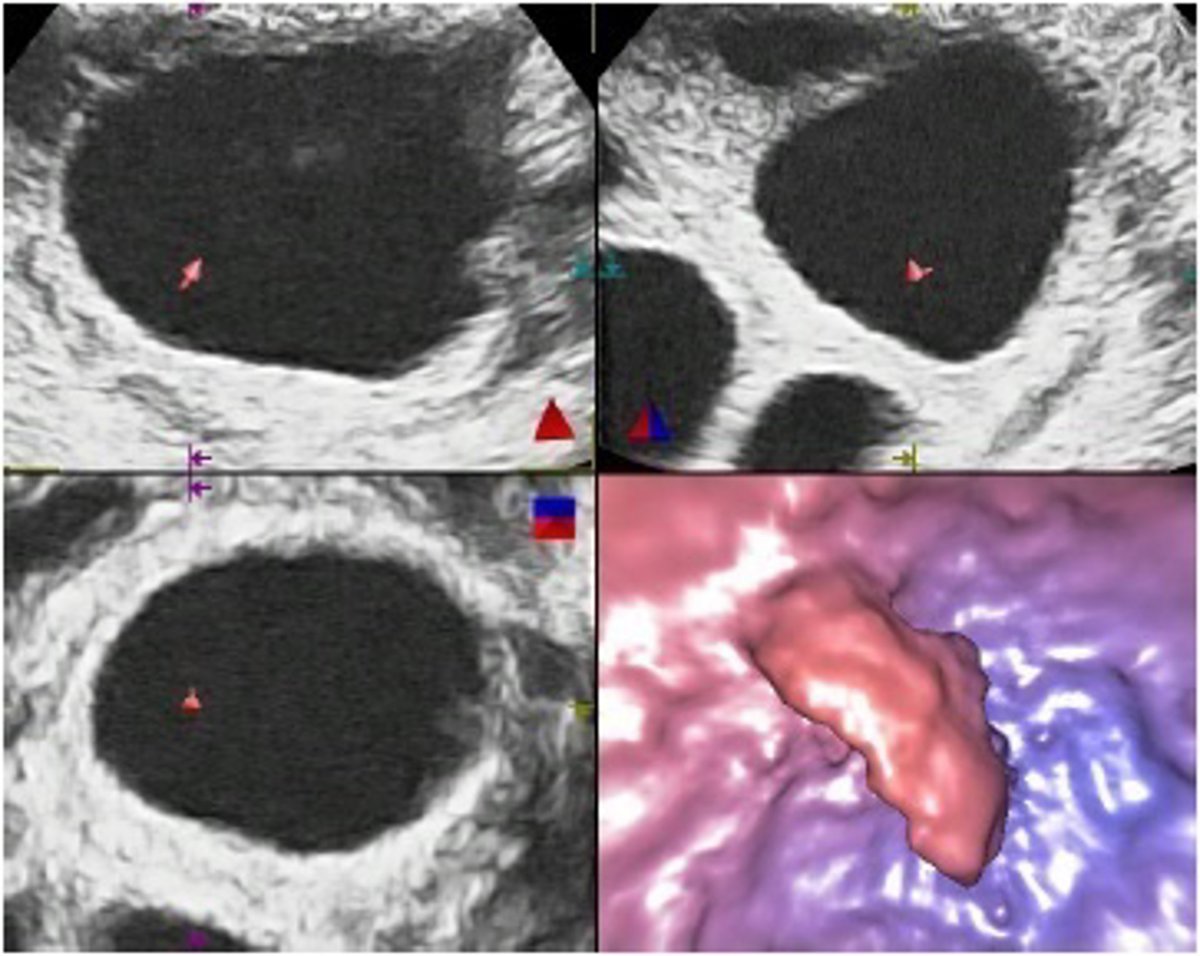

Foliculoscopia virtual

Un equipo de investigadores de la Universidad de Granada y de la Clínica Margen de esta ciudad ha dado a conocer una nueva técnica, denominada Foliculoscopia virtual, que permite saber si hay óvulos, y cuántos, antes de proceder a una punción de ovarios en los tratamientos de fecundación in vitro.

La nueva técnica de imagen médica permite predecir el número de óvulos que se podrán obtener mediante la punción de ovarios. De esta manera, la punción sólo se realizará en aquellos casos en los que se ha confirmado la existencia de óvulos, evitando los inconvenientes de todo tipo, físicos y emocionales, y los gastos innecesarios que se producen actualmente cuando la punción no tiene éxito, según detalla en una nota la clínica.

Los folículos son cavidades presentes en los ovarios en las que se desarrollan los óvulos y se pueden visualizar mediante un examen ecográfico. Para la fecundación in vitro se utilizan tratamientos hormonales que aumentan el número de los folículos y estimulan su crecimiento. En teoría, cada folículo tendría que contener un óvulo.

La técnica de foliculoscopia virtual, desarrollada en Granada y ya disponible, permite proporcionar a las mujeres la información necesaria para tomar esta decisión con pleno conocimiento de las cosas.